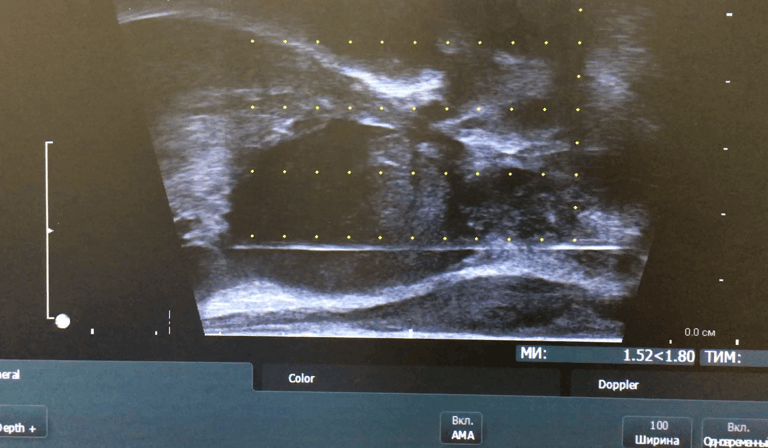

Для діагностики раку передміхурової залози проводиться трансректальна або промежина (трансперинеальна) біопсія, що, за Європейськими стандартами, має обов’язково робитися під УЗД контролем.

Відповідно до рекомендацій Європейської асоціації урології біопсія передміхурової залози під контролем УЗД є стандартною діагностичною процедурою. Лікарю необхідно лише обрати один із двох способів виконання цієї маніпуляції - трансректальний чи промежинний.

Відео: промежинна біопсія простати під УЗД контролем

Про важливу роль аналізу крові на ПСА та мультипараметричної МРТ, як проходить процедура та чому промежинна біопсія простати краща за трансректальну розповідає у відео д.мед.н., лікар-онкоуролог Юрій Васильович Вітрук.

Процедура промежинної біопсії загалом триває до 10 хвилин в залежності від кількості виконаних точок взяття біопсії.

В нашому «Центрі сучасної урології», як правило, біопсія проводиться під внутрішньовенним загальним знеболенням – і проводиться саме промежинна біопсія передміхурової залози за стандартом з 12 ділянок (6 з лівої і 6 з правої долі передміхурової залози).